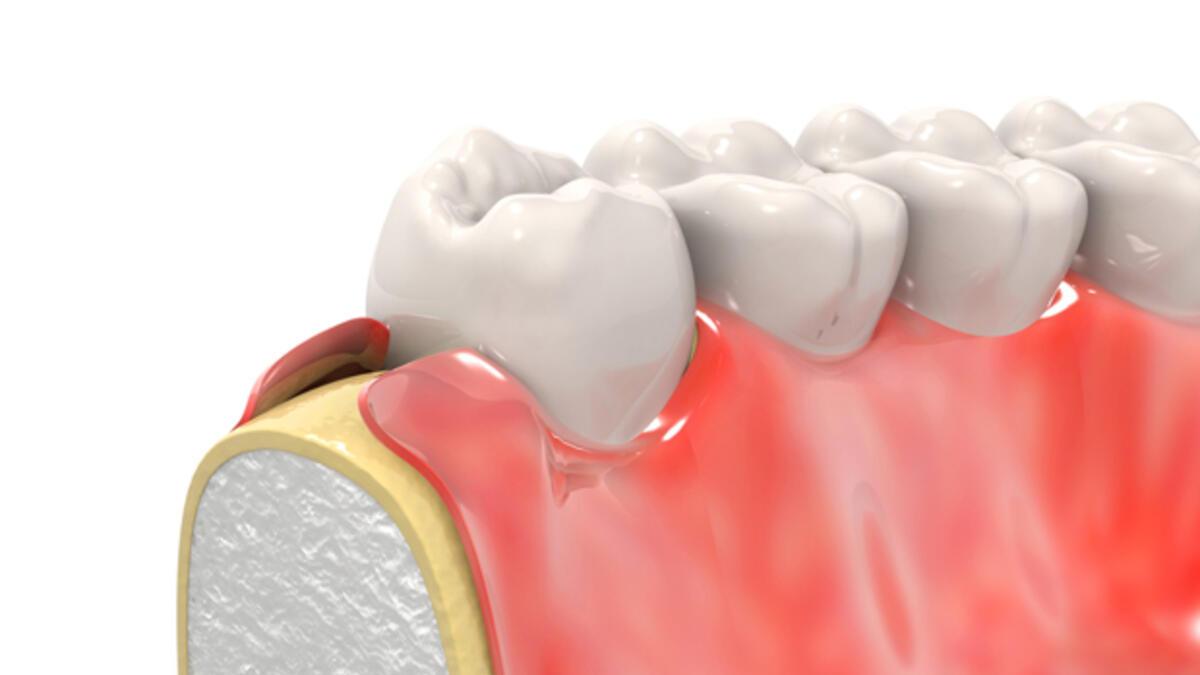

Dis Eti Sismesi Ve Cozumleri Aciklamali Ve Gorselli Anlatim

Dis Eti Sismesi Ve Cozumleri Aciklamali Ve Gorselli Anlatim

Dis Eti Sismesi Ve Cozumleri Aciklamali Ve Gorselli Anlatim

Dis Eti Sismesi Ve Cozumleri Aciklamali Ve Gorselli Anlatim